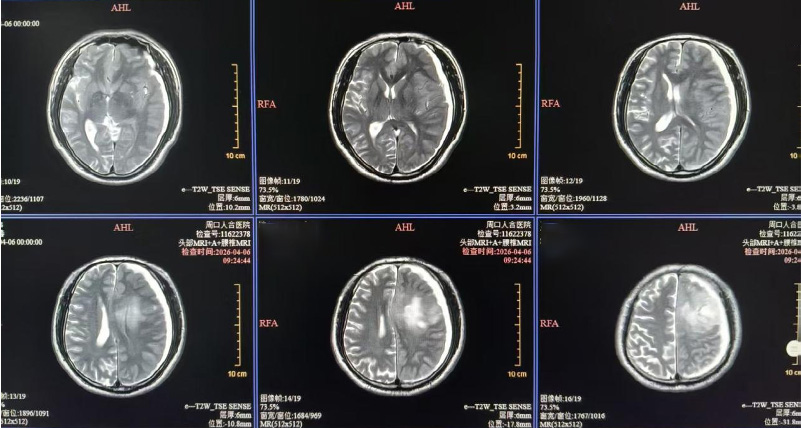

患者因“突发剧烈头痛、意识淡漠、肢体无力”入院,接诊医生当即启动急诊绿色通道,快速完成检查,结果显示:左侧额顶叶占位并局部出血、硬膜下血肿,中线结构移位——这意味着患者颅内有活动性出血,随时可能引发脑疝,危及生命,具备明确急诊手术指征。

术前检查